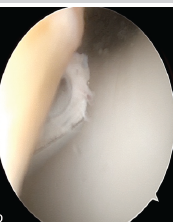

Knee Arthroscopy in Morbidly Obese Patients: Perioperative Challenges and Technical Considerations to Optimize Outcomes

M R Abinav , A K Sanjay , Vignesh Murali , Praveen Ravi , Suresh Perumal , Arumugam Sivaraman

………………………………p.371-378